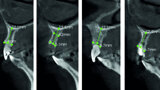

Fig. 4: Pre-op CT analysis.

Fig. 50: CT analysis post-op.